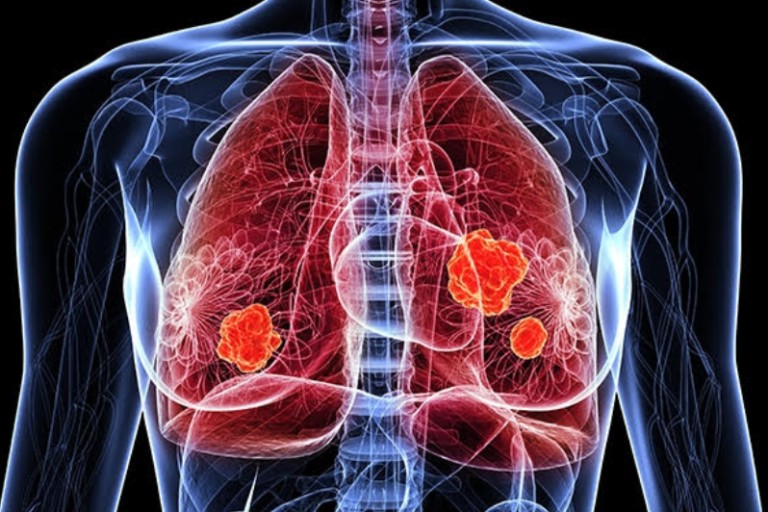

폐렴 증상 폐렴은 폐의 세균, 바이러스, 곰팡이 등 감염으로 인해

폐포(폐 속의 공기 주머니)에 염증이 생기고, 고름이나 액체가 차는 질환입니다.